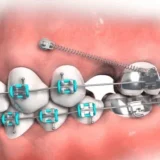

Ngày nay, nhu cầu làm đẹp và chăm sóc sức khỏe răng miệng ngày càng được chú trọng. Trong đó, chụp sứ là một phương pháp được